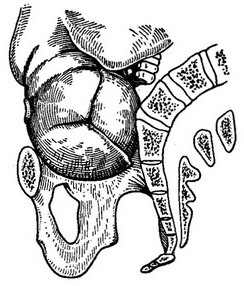

З початком пологової діяльності головка, як і при нормальних пологах, встановлюється у вході в таз у злегка зігнутому положенні своїм стрілоподібним швом в поперечному розмірі. Але, зустрічаючи перешкоду у зв'язку із зменшенням істинної кон'югати, вона затримується біля входу. Надалі, по мірі розвитку пологової діяльності, відбувається її пристосування до особливостей будови тазу і подолання виниклої перешкоди. Воно полягає в наступному: зустрівши на своєму шляху перешкоду, голівка робить два пристосувальних руху. Перше полягає в деякому її розгинанні (рис. 47) та друге - у зміщенні стреловидной шва від провідної осі тазу до лона або крижів (рис. 48, 49). Якщо стріловидний шов відхиляється назад (рис. 49,а, 50, 51),то у вхід тазу раніше вступає передня тім'яна кістка (права чи ліва, в залежності від позиції плода), а задня - затримується біля мису. Таке зміщення стреловидной шва називається переднім асинклитизмом (або негелевским схилянням, по імені автора - Negelle описав таке вставлення голівки). Навпаки, якщо стріловидний шов відхиляється наперед, тобто до лона, то у вхід тазу вставляється задня тім'яна кістка, а передня затримується біля лона. Це зміщення стреловидной шва називається заднім асинклитизмом (або лицмановское відмінювання) (рис. 49,6), по імені автора, її описав (Litzmann).

![]() Рис. 50. Вставляння голівки при плоскому тазі - передній асінклітізм. Стріловидний шов відхилений до мису, «передня» половина черепа нижче «задній». |

![]() Рис. 51. Переднетеменное вставляння голівки при плоскорахітіческій тазі (вид знизу). |